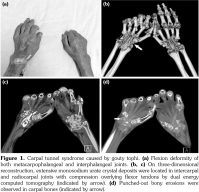

A 54-year-old male patient was admitted to our department with palmar numbness and disability for two years. He had a history of gout for 30 years but received no treatment. Physical examination revealed obvious subcutaneous tophi and thenar muscle wasting. Flexion deformity of his metacarpophalangeal and interphalangeal joints is shown in Figure 1a. Positive Tinel’s sign and Phalen’s maneuver were present. Routine laboratory test showed high level of uric acid (608 μmol/L). The electrophysiological examination revealed sensory and motoring demyelinating and axon lesions in both median nerve, especially in the right hand, which supported the diagnosis of CTS. Furthermore, DECT showed extensive monosodium urate crystals in the intercarpal and radiocarpal joints with compression overlying the flexor tendons (Figure 1b, c). We also observed punched-out bony erosions in the carpal bones (Figure 1d). These aspects indicated severe and typical CTS caused by gouty tophi, which was further confirmed by biopsy of fine-needle aspiration (Figure 2). Surgery was recommended, but the patient refused to undergo surgery and chose to receive febuxostat. Uric acid level had decreased in the next six-month follow-up with little improvement for his numbness and deformity. A written informed consent was obtained from the patient.